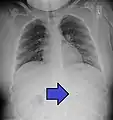

سکه ای که در AP CXR در مری دیده میشود